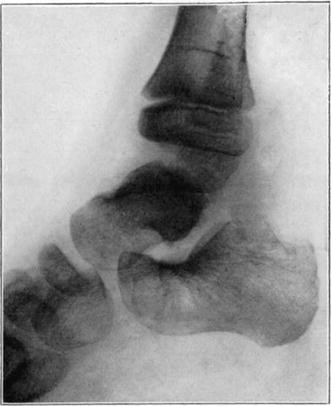

Case 2. Seventy-four days after fracture of neck of astragalus, posterior dislocation of body, and reduction by operation. Body necrotic and retained normal density. Atrophy of disuse of other bones. Bony union of fracture.

Case 2. One hundred and sixty days after fracture. Body slightly reduced in density near fracture due to invasion from neck.

Case 3. Fresh fracture of neck of astragalus and chip off superior and posterior portion of os calcis.

Case 3. Two hundred and seventy-four days after injury. Fracture of astragalus united. Superior and posterior part of body broken down and irregular while remaining portion dense and transformed. Indicative of necrosis of body with secondary changes.

Case 3. Eighteen months after injury, showing a defective but gradually reforming articular portion of the body of the astragalus.

The blood supply of the astragalus is derived mainly from a branch of the arteria dorsalis pedis which traverses the sinus tarsi lateral to the neck and breaks up to enter the bone near the junction of the neck and body along the lateral and inferior surfaces. There are very small branches entering the bone mesially and posteriorly at points of ligamentous and capsular attachments. Apparently when there is a fracture along the junction of body and neck the important vessels to the body are interrupted and there may be insufficient circulation through the remaining vessels, so that aseptic necrosis of a large part or all of the fragment follows. It is evident from the partial collapse which occurred in Case 3 that when necrosis of the body is diagnosed, the limb should be protected from weight-bearing for at least several months,—until union, revascularization, and transformation of necrotic area has been largely brought about. It seems probable that some of the bad results that have been reported in fracture of the neck of the astragalus, either united or ununited, have been due to overlooked aseptic necrosis of the body.